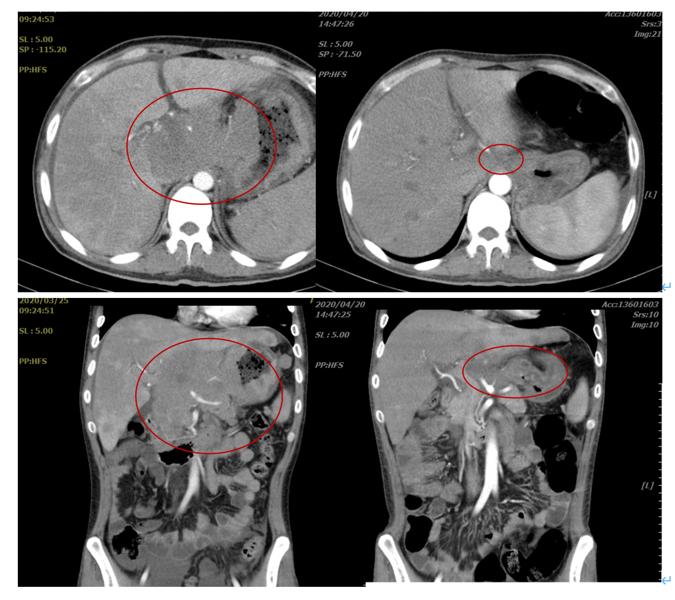

2020-4-20复查腹部增强CT(图三所示):腹腔、肝门区及腹膜后见多发肿块影.增强后轻度强化,融洽成大块,大小约40X43X44mm,较前明显缩小,肿块与胰腺关系密切,主胰管无明显扩张.胃壁不规则稍增厚并强化。

图三

通过上述影像学变化我们可以看到BV-IVE方案治疗后,患者瘤灶明显缩小(如上图三)。该患者经过减瘤治疗后续进入CAR-T治疗。从此病例我们可以看出CD30阳性的弥漫大B患者,对BV的治疗反应还是比较好的。